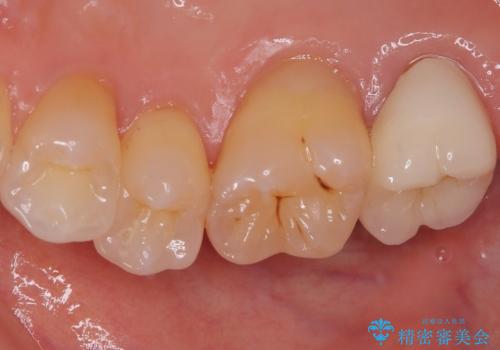

根管治療を行った奥歯は、再発防止や残された歯質を守るため、クラウンによる補綴治療が必要となります。

補綴後6ヶ月経過しレントゲンを撮影したところ、根尖周辺の病変が消失していることが確認できました。